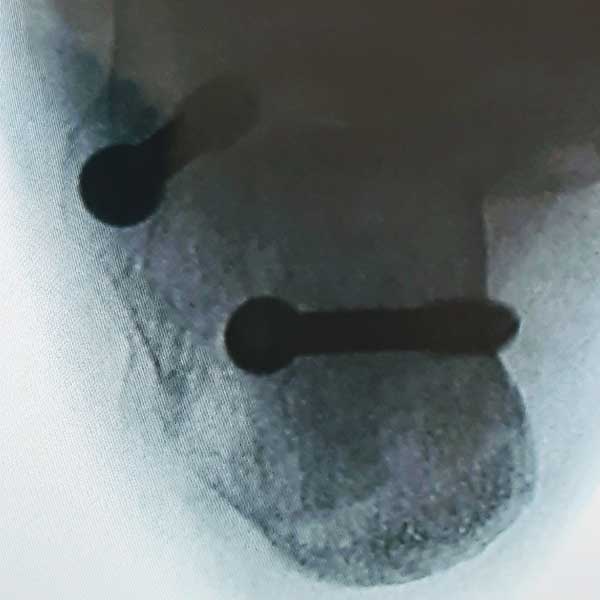

Case:3 Hoffa's Fracture

Per-Op